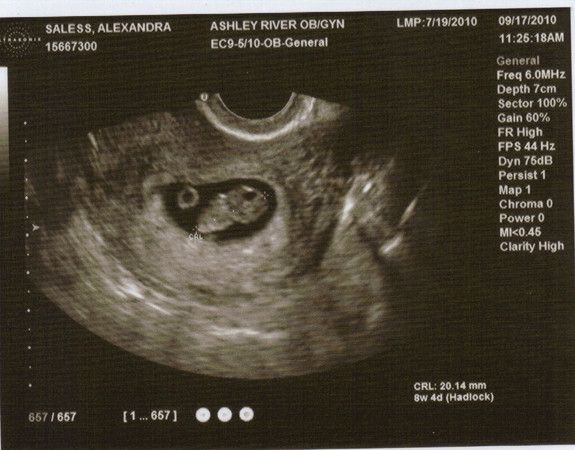

8W 4T Lexabailey's erstes US-Bild!

17.09.2010

20.14mm gross

Herzschlag 166 bpm

Man sieht noch den Dottersack und beim Arzt auf dem Ultraschallgeraet konnte man schon super die kleinen Ansaetze der Haende und Fuesse sehen, sieht man auf dem Bild hier leider nicht so gut.